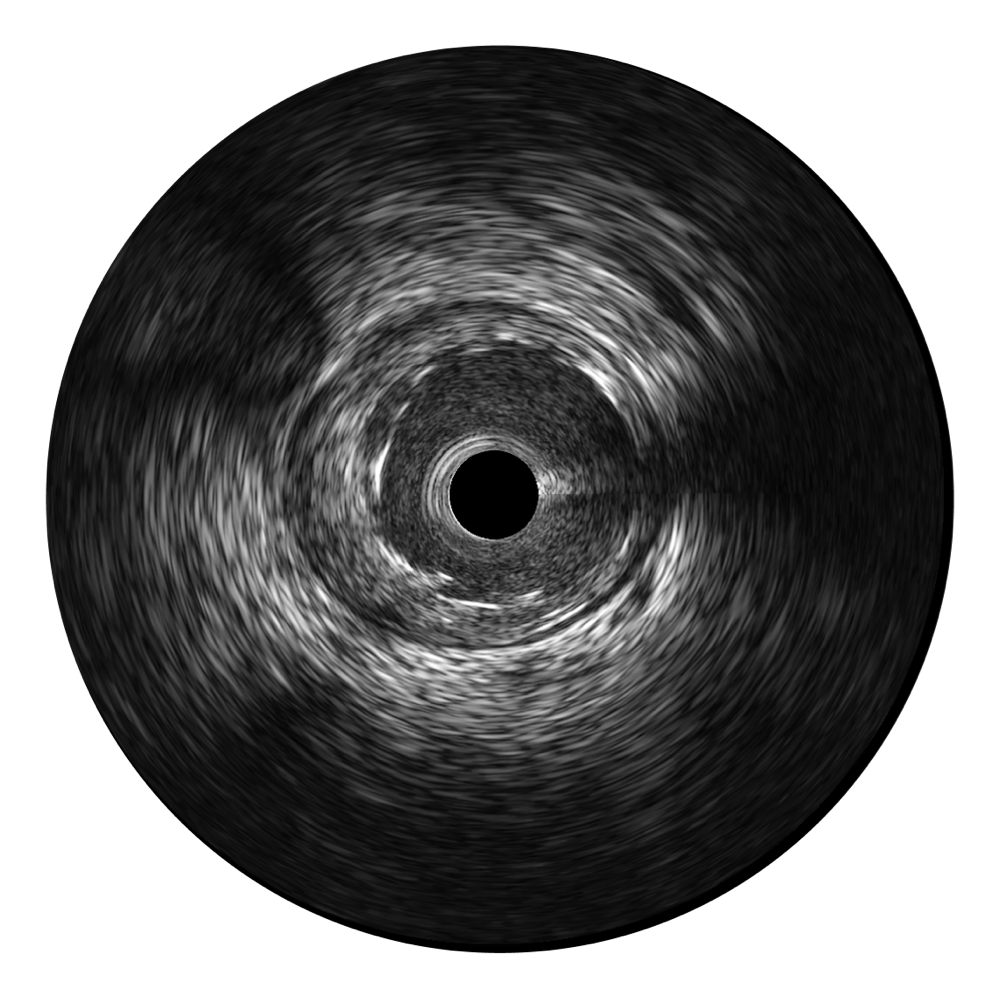

• 银河集团官网宽频IVUS图像

对比传统IVUS导管成像,银河集团官网宽频IVUS图像的近场支架梁显影更细腻,远场中膜外血管仍清晰可辨,兼顾远中近,兼顾分辨力与穿透深度